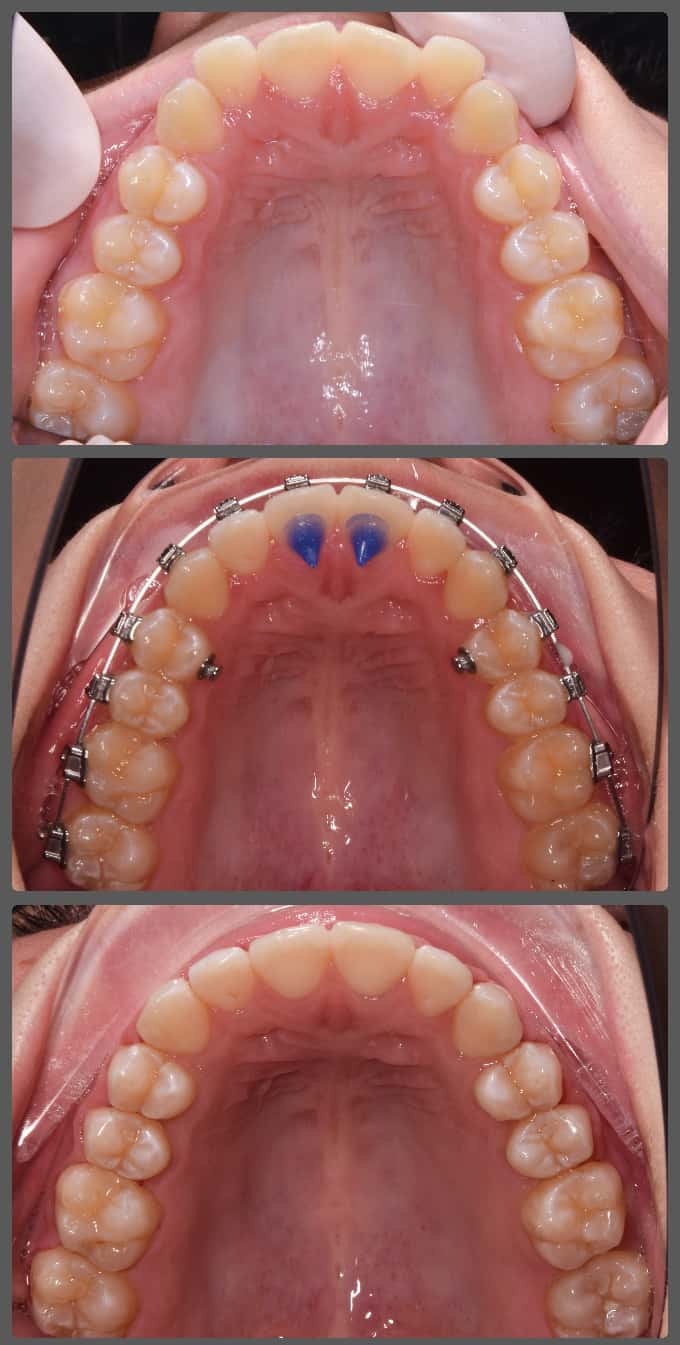

Bálint a 90 fokban elfordult jobb felső kismetszője miatt keresett meg engem. A vizsgálatokat követően kiderült, hogy a probléma ennél jóval komplexebb: súlyos keresztharapást, súlyos mélyharapást és felső rágósík billenést diagnosztizáltam nála. Alsó-felső H4 önligírozó fogszabályozó készülék, intermaxilláris gumihúzás és elülső harapásemelők segítségével korrigáltuk az eltéréseket. A bal oldali rágósík billenést fogszabályzási miniimplantátum alkalmazásával oldottuk meg. A bal felső-elülső fogakat felfelé mozgattuk, a miniimplantátumhoz húzva. Bálint esete igen komplex volt, ám kiváló együttműködésének köszönhetően 26 hónap alatt végeztünk a kezelésével (beleértve a 2-3 hónapos COVID-19 miatti leállást is). Az eredmény úgy gondolom magáért beszél!